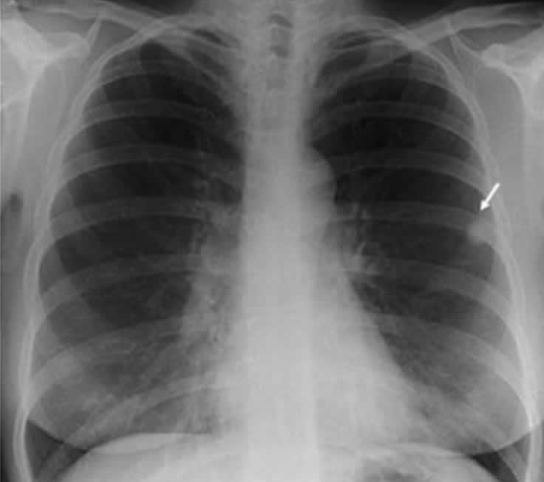

CXR상에 나타난 정보를 점수화하여 TB granuloma가 존재하는 환자의 분포를 추정하는 기계를 만든다고 하자. 아래 그림에서는 사진 우측에 보이는 화살표가 granuloma에 해당하는 영역이다.

이 기계를 만들 때, 알고리즘을 다음과 같이 설정한다고 하자.

granuloma인지 판단하기 위해 x라는 점수를 설정하자

1. 위치: lung에 해당하는 영역에 있으면 점수 추가

2. 형태: 주변과 색깔이 다르며 구형, 타원형에 해당한다면 점수 추가

3. 색깔: 주변에 비해 흰색의 정도에 따라 점수 추가

이때, ML과 MAP를 사용하는 것은 각각 아래의 의미이다.

- ML: 어떤 점수 x가 나온 CXR에 대해, granuloma 환자에서 그 점수가 나올 확률 P(x | granuloma)과 정상인에게서 그 점수가 나올 확률 P(x | ~granuloma)의 값을 비교하여 더 높은 것을 산출한다.

- MAP: 어떤 점수 x가 나온 CXR에 대해, granuloma일 확률 P(granuloma | x) 과 정상일 확률 P(~granuloma | x)을 비교하여 더 높은 것을 산출한다.

MAP에서 P(granuloma | x)에는 어떤 정보가 들어가 있는가? 가능도 P(x | granuloma)도 들어가 있지만, 사전 확률(prior)에 해당하는 P(granuloma)도 들어가 있다. 따라서, 기존에 granuloma 환자의 비율이 어느 정도 된다는 사전 정보가 있어야 사용할 수 있다. 또한 이 값에 따라 모델의 분류 기준이 바뀔 수 있다. 즉, MAP를 쓰면 이 모델을 대한결핵협회에서 사용할 때와 콜롬비아(2021 결핵 사망률 1위 국가)에서 사용할 때 분류 기준이 다르다. 반면, ML을 쓰면 P(granuloma)를 고려하지 않기 때문에 전 세계 어디서나 분류 기준이 같을 것이다.